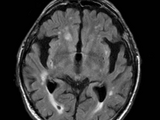

it is GUI based program used to detect Alzheimer in MRI SCAN IMAGE

Alzheimer's disease is the most common type of dementia. It is a progressive disease beginning with mild memory loss and possibly leading to loss of the ability to carry on a conversation and respond to the environment. Alzheimer's disease involves parts of the brain that control thought, memory, and language. Scientists do not yet fully understand what causes Alzheimer’s disease. There likely is not a single cause but rather several factors that can affect each person differently.Age is the best known risk factor for Alzheimer’s disease. Family history—researchers believe that genetics may play a role in developing Alzheimer’s disease. However, genes do not equal destiny. A healthy lifestyle may help reduce your risk of developing Alzheimer’s disease. Two large, long term studies indicate that adequate physical activity, a nutritious diet, limited alcohol consumption, and not smoking may help people. To learn more about the study, you can listen to a short podcast. Changes in the brain can begin years before the first symptoms appear. Researchers are studying whether education, diet, and environment play a role in developing Alzheimer’s disease. There is growing scientific evidence that healthy behaviors, which have been shown to prevent cancer, diabetes, and heart disease, may also reduce risk for subjective cognitive decline. Here’s 8 ways. What are the warning signs of Alzheimer’s disease? Alzheimer’s disease is not a normal part of aging. Memory problems are typically one of the first warning signs of Alzheimer’s disease and related dementias.